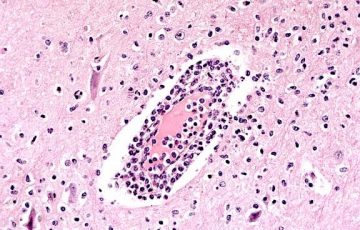

Jak kapsulární kontraktura vzniká

Kolem každého cizího tělesa, tedy i kolem každého prsního implantátu, tělo vytvoří vazivové pouzdro. Jde o přirozenou a žádoucí reakci. Pouzdro kolem implantátu by ale mělo zůstat tenké a nezjistitelné pohmatem.

U některých žen reaguje tělo na vložení implantátu tvorbou pevného a tuhého vazivového pouzdra. Pokud se toto pouzdro začne smršťovat, říkáme komplikaci „kapsulární kontraktura“.